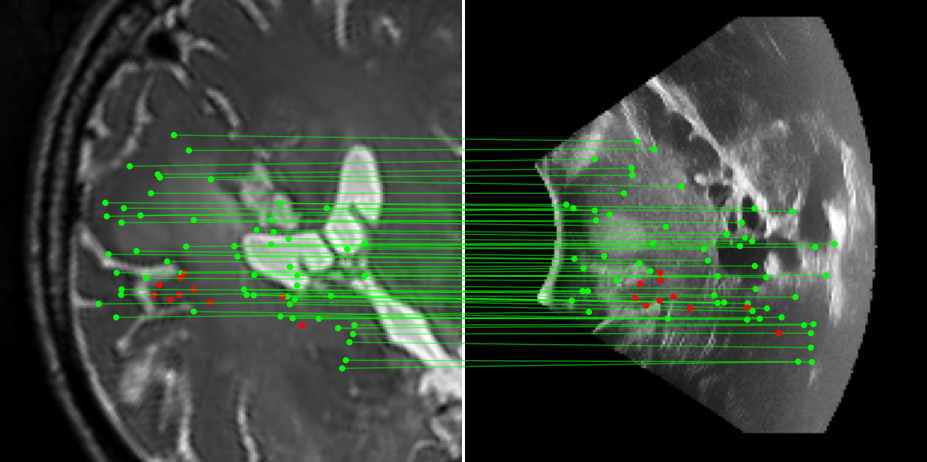

Figure 3: Examples of matching on three cases, one per column (MR on left and US on right). From top to bottom: SIFT+Cosine, MIND+Cosine, SP+Cosine, SP+LG, Ours+LG, Ours+Cosine. Correct matches recovered by each method are shown in green lines and mismatched are shown with a red dot.

To evaluate the performance of our model against existing image methods, we compared it to three approaches: SIFT [16], which remains the standard for keypoints matching, SuperPoint (SP) [3] built using a self-supervised learning approach and MIND [10], a modality-invariant descriptor for medical imaging, that although not designed for 1-to-1 keypoint matching, is extensively used for multimodal medical image registration through grid regularizing. We use SIFT and SP as keypoints detectors and descriptors, while we combine MIND with SP keypoints since it only provides a descriptor. We match these descriptors using both Cosine similarity and the deep neural network LightGlue (LG) [15] when possible (SP and Ours). Results reported in Table 2 and shown in Fig. 3 show that our approach outperforms these methods in terms of matching score, precision, and number of matched points. We only report results on three cases for readability reasons. Associating our descriptor with Cosine and LG reached similar performance depending on the metric.